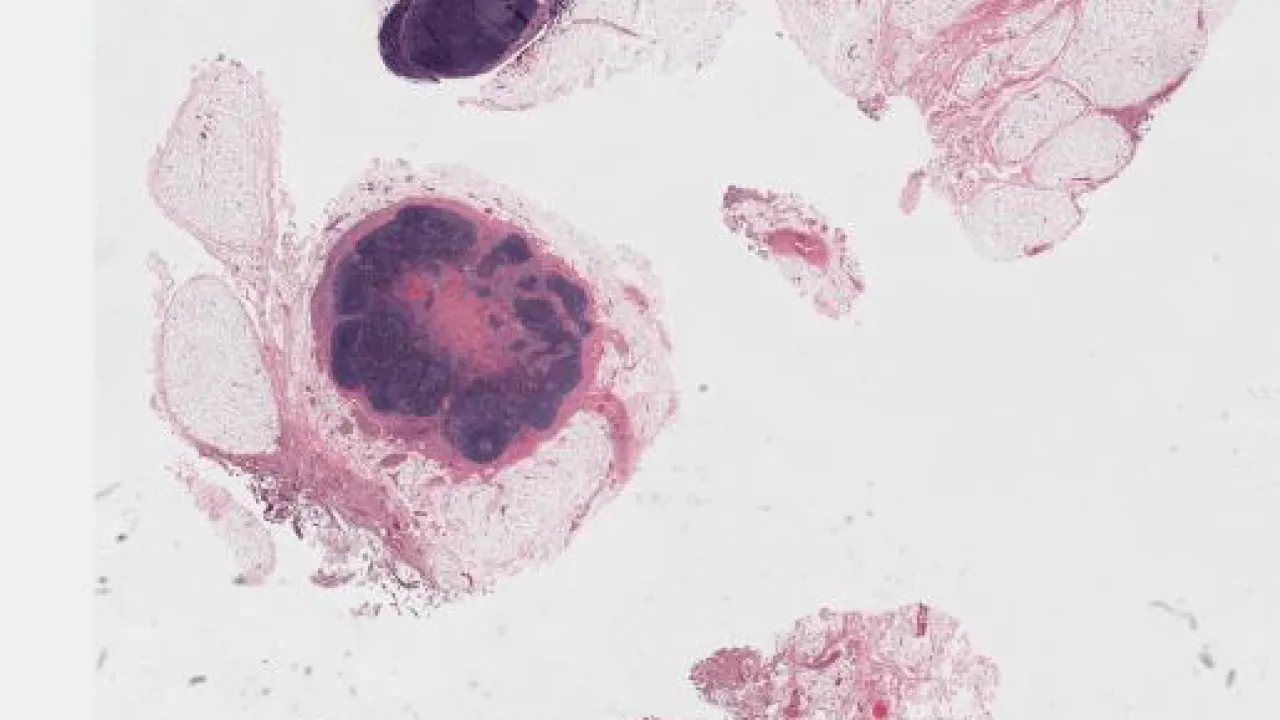

Lymph Node, Nodular lymphocyte predominant Hodgkin lymphoma, H&E stain